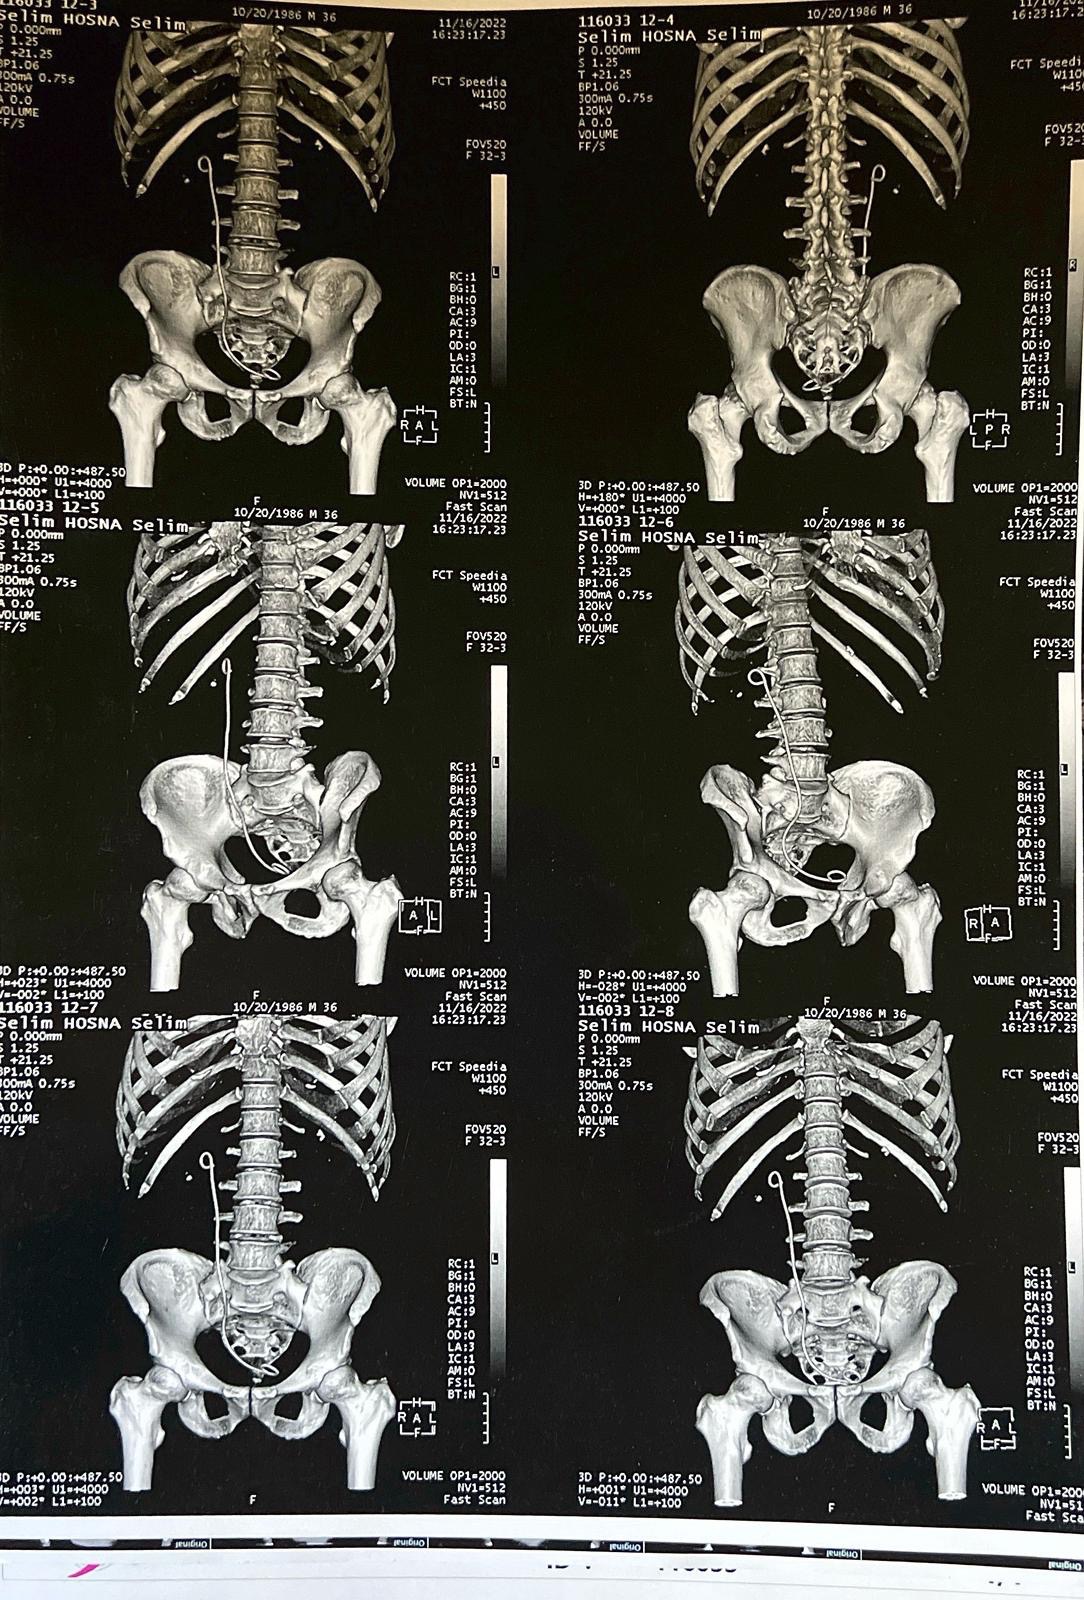

I am currently suffering from a severe kidney stone measuring four centimeters in length, a condition that is causing me excruciating pain on a daily basis. Due to the severely limited healthcare infrastructure in Gaza, there are no available facilities or specialists capable of performing the necessary surgical procedure to remove the stone.